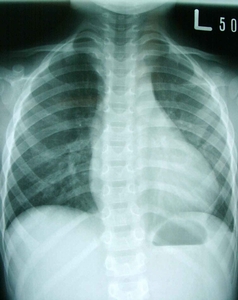

術前X光照片

漏斗胸為最常見的先天胸壁畸型,此漏斗胸由外表判斷,可小至放置一個網球而不會掉落地面,可大至兩乳之間皆凹陷,嚴重影響心肺功能。由於胸肋骨的畸型,而造成胸骨向脊椎方向凹陷,甚至最嚴重的畸型是胸骨與脊椎骨相當靠近,造成原先位在兩者之間的心臟被推向左邊,肺部的擴張空間變小,甚至會影響心肺功能,而被壓迫的心臟及肺部的位置及形狀,可由電腦斷層掃描明顯診斷之。